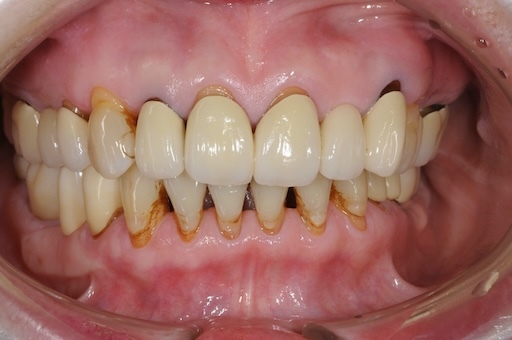

| 治療内容 | プラークコントロール不良なため歯周治療を行い、残存歯を極力温存し、欠損部インプラントを施し咬合再構成を行う。 プロビジョナルレストレーションによる咬合関係を模索した後、全顎にわたりセラミックによる補綴治療、その後メインテナンスに移行 |